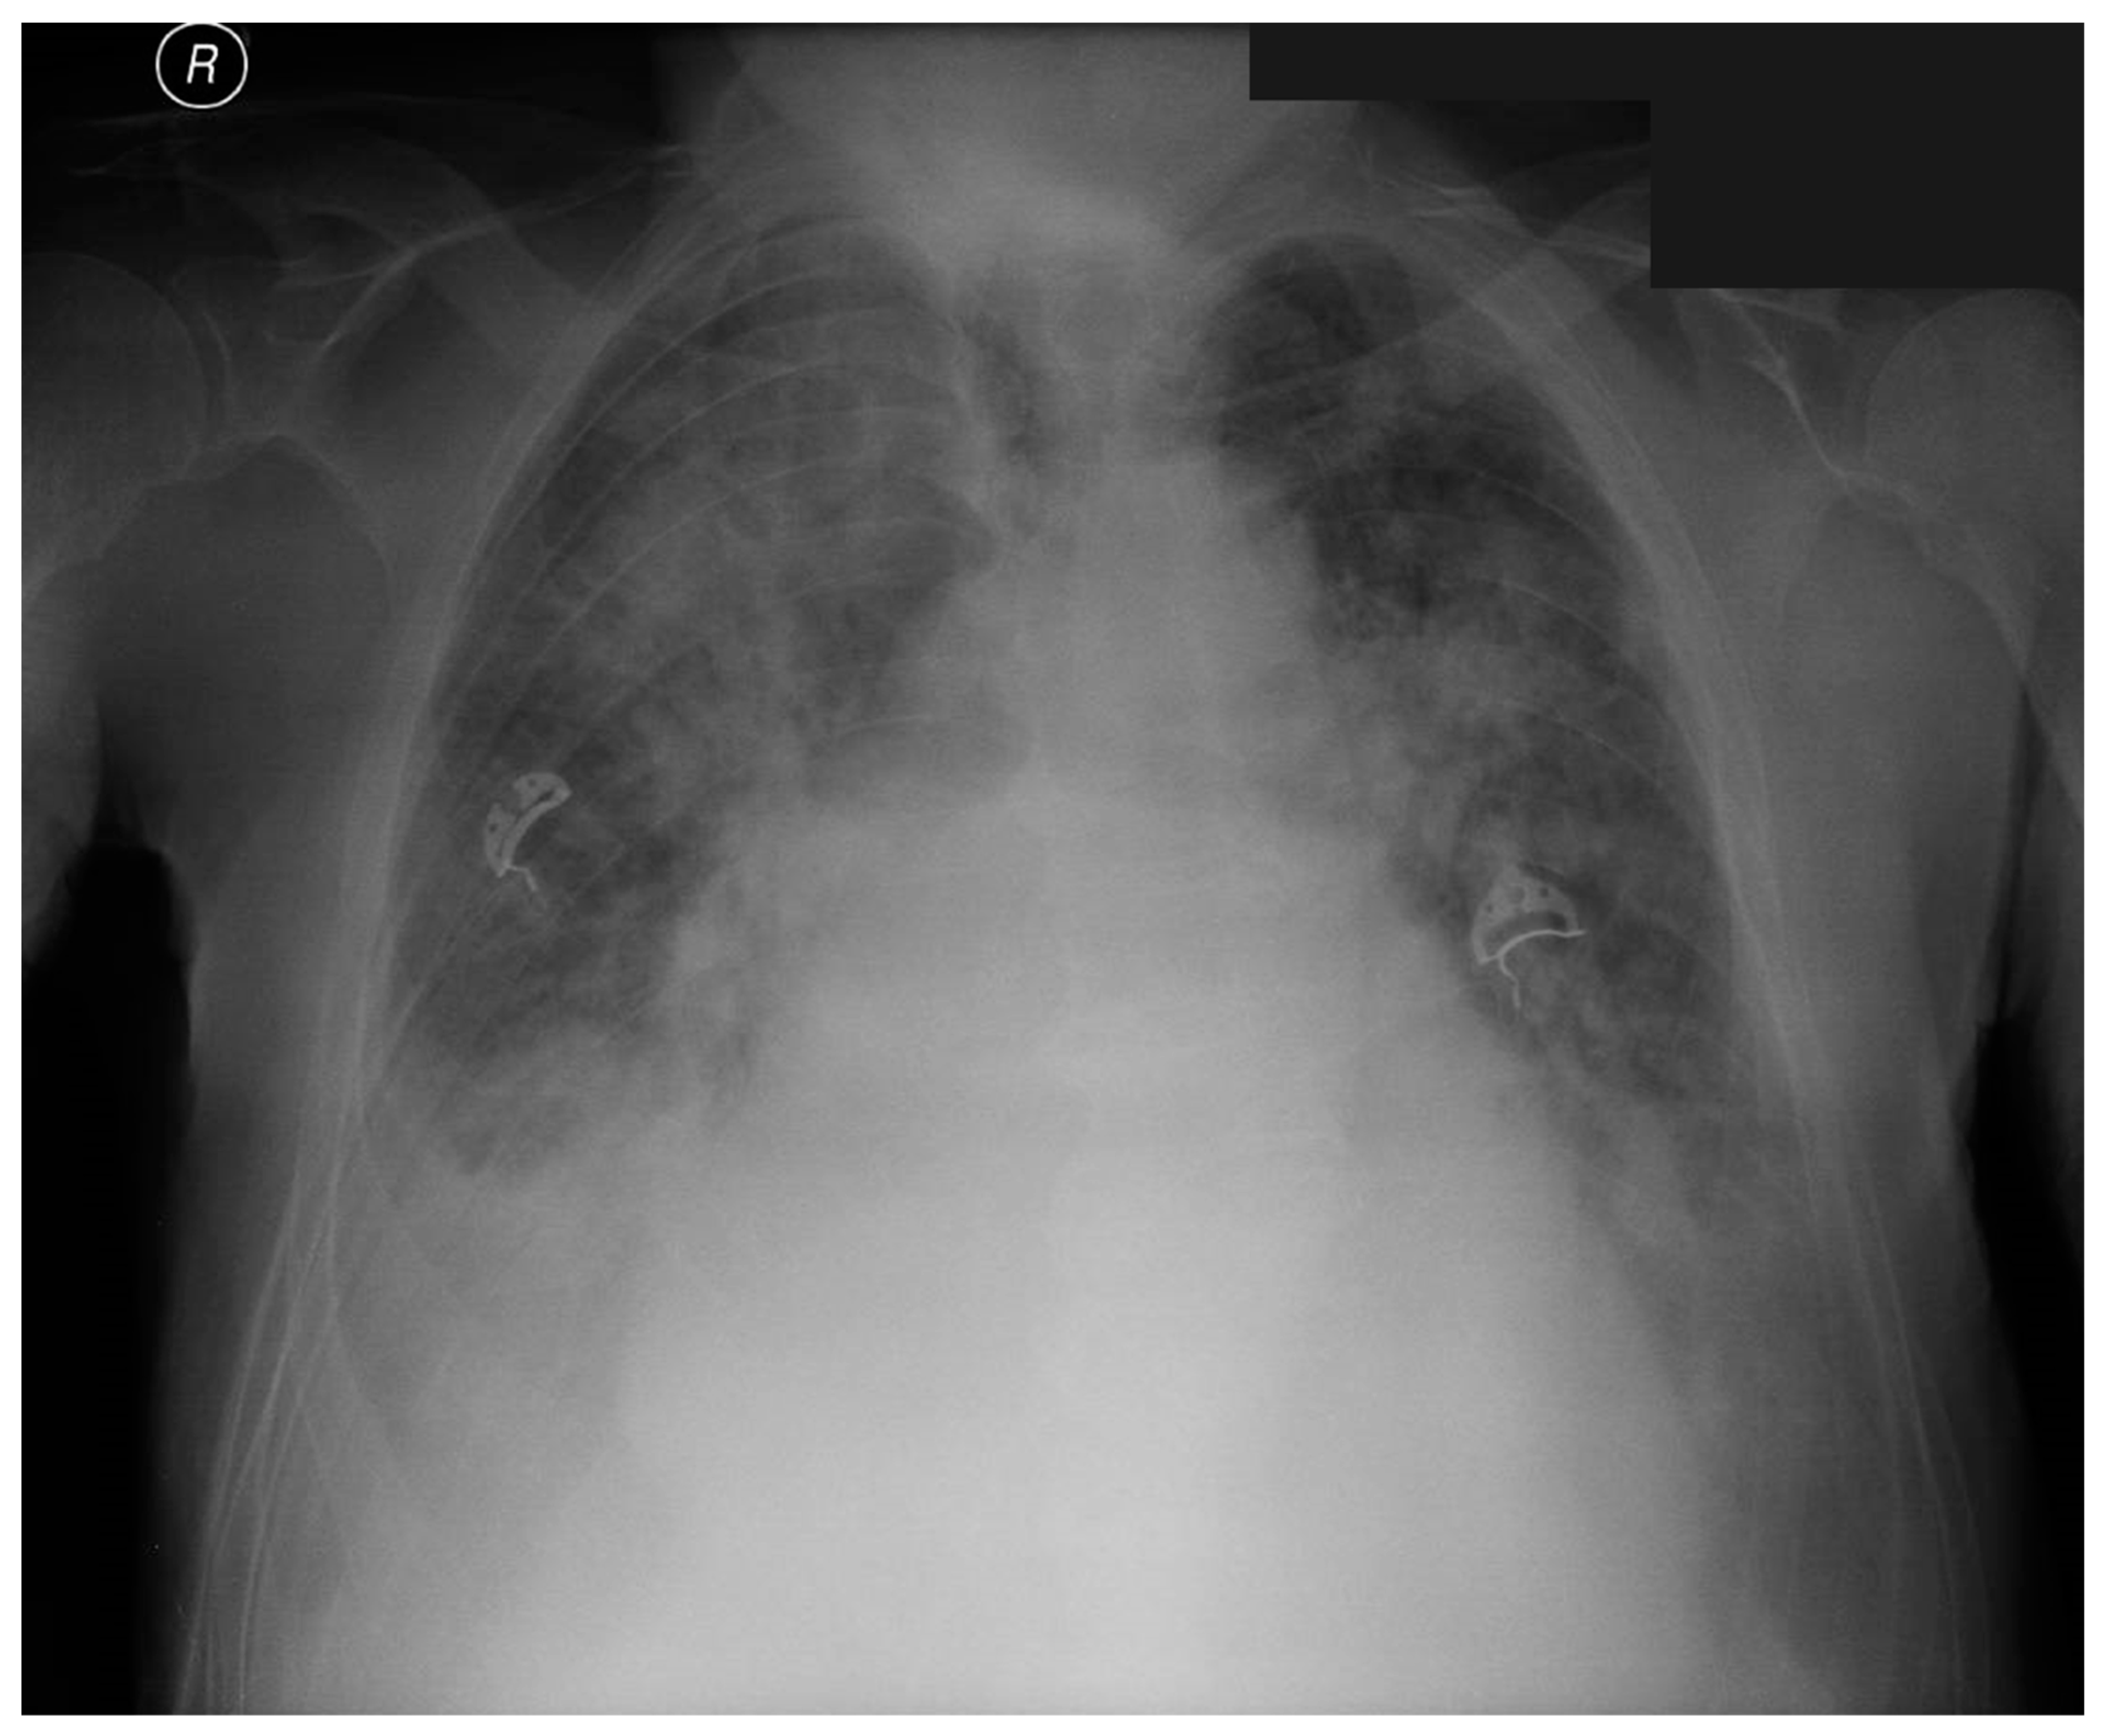

2. Case Report